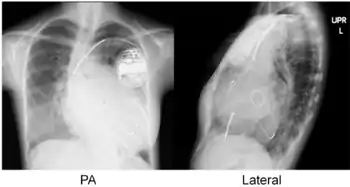

Chest radiographs of cardiac resynchronization therapy with defibrillator (CRT-D) in an individual with dilated cardiomyopathy after mitral valve replacement (MVR). The leads are:

- Atrial lead at the right appendage

- Right ventricular lead at the apex

- Left ventricular lead through the coronary sinus.[7]